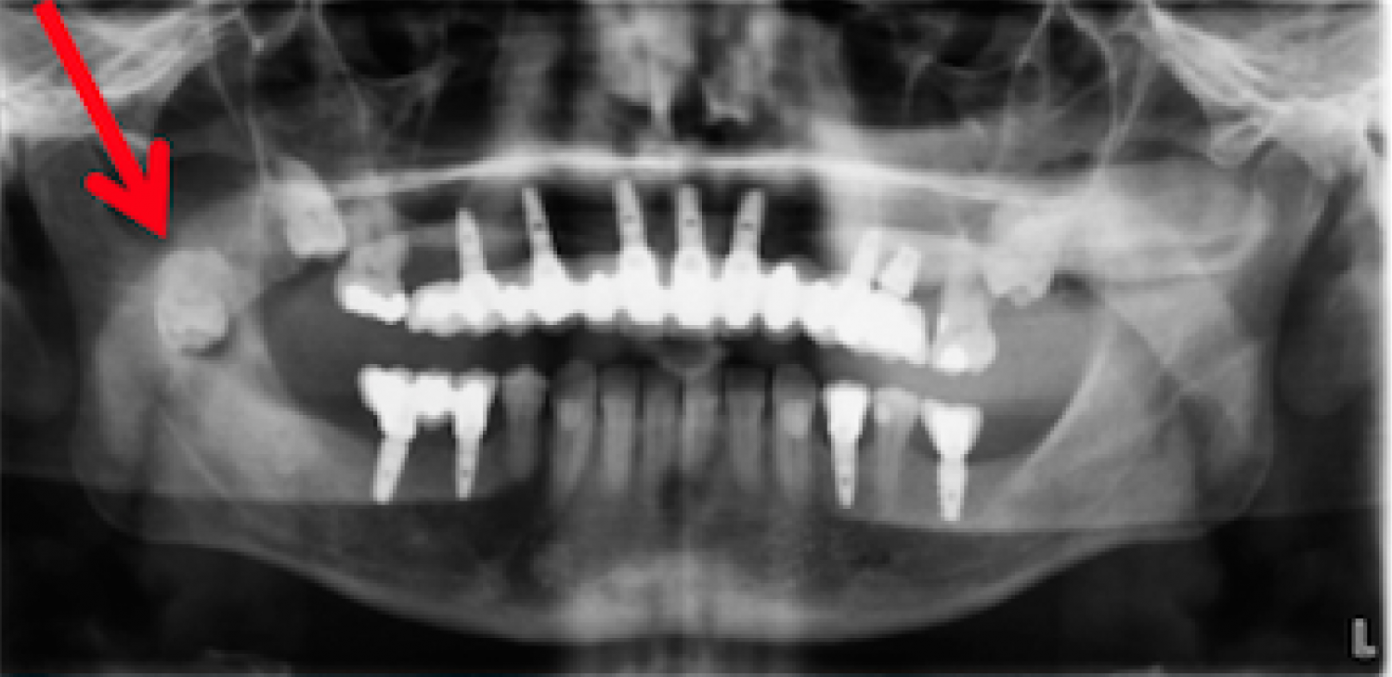

From journal.medizzy.com

Infected Ectopic Wisdom Tooth MEDizzy Journal What Is Ectopic Eruption Of Teeth Ectopic eruption is a disturbance in which the tooth does not follow its usual course. An ectopic eruption is a tooth following a path that deviates from the norm. Abnormal eruption, also known as ectopic eruption or ectopia, is a disturbance in tooth development and is when a tooth erupts through the gum out of the proper position. Ee of. What Is Ectopic Eruption Of Teeth.